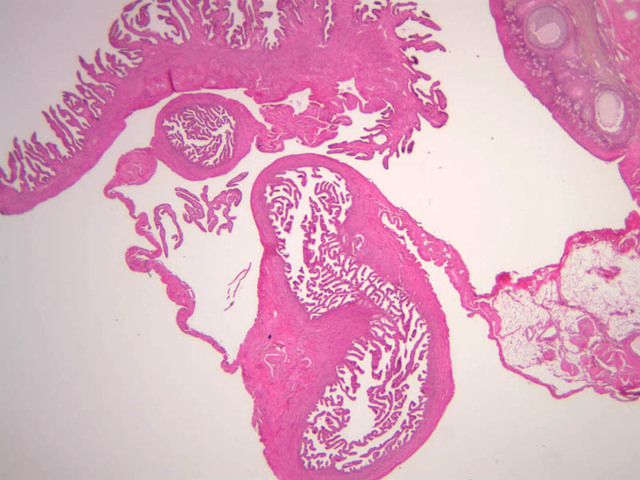

The wall of the uterine tube consists of three layers; a mucosa, a muscularis, and an adventitial/serous coat (B-96 [2.5x, 10x-labeled, 20x, 40x] [2.5x, 10x, 20x, 40x]; B-97, monkey uterus [2.5x, 10x, 20x, 40x]). The mucosa is organized into folds that vary in their degree of complexity with the tube regions. The mucosa is lined by a simple columnar epithelium consisting of two cell types, ciliated and non-ciliated, secretory (B-93 [10x, 20x, 40x-labeled]). The mucosal lamina propria consists of somewhat loose connective tissue and is highly vascular. No muscularis mucosae are present. The muscularis consists of two layers of smooth muscle, the inner being oriented in a circular fashion and the outer longitudinally.

The structure of the uterine tube is under the control of, and responds to, cyclic changes in the levels of steroid hormones. Structural alterations to provide favorable transport for the oocyte commence anew with the beginning of each cycle and peak at mid-cycle just before ovulation. These include increases in height and number of the ciliated cells as well as active secretion in the secretory cell. For the remainder of the cycle thereafter, dedifferentiation occurs. The cyclic changes occur to a greater extent in the upper ampulla and infundibulum. The margin of the infundibulum is drawn out into numerous finger-like processes called fimbrae. Microscopic examination of these will reveal that within the lamina propria are numerous large blood vessels, especially veins, as well as bundles of smooth muscle forming an intervening network. At the time of ovulation, the vessels become enlarged with blood, causing turgidity, which when combined with smooth muscle contraction brings the infundibular opening into close apposition with the ovarian surface.